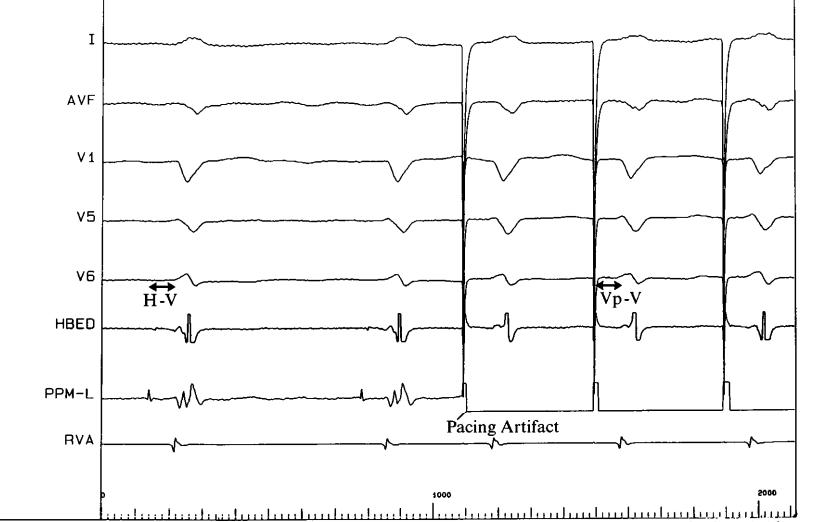

Evidence - LB versus LOT

QRS duration - LOT CRT

qrs_duration_lot.jpg

Jastrzębski M, Moskal P, Huybrechts W, Curila K, Sreekumar P, Rademakers LM, Ponnusamy SS, Herweg B, Sharma PS, Bednarek A, Rajzer M, Vijayaraman P. Left bundle branch-optimized cardiac resynchronization therapy (LOT-CRT): Results from an international LBBAP collaborative study group. Heart Rhythm. 2022 Jan;19(1):13-21. doi: 10.1016/j.hrthm.2021.07.057.

lb_lot.jpg

Comparison of electrocardiographic parameters between left bundle optimized cardiac resynchronization therapy (LOT-CRT) and left bundle branch pacing—cardiac resynchronization therapy (LBBP-CRT). Chinmay Parale, Dinakar Bootla, Ashish Jain, Santhosh Satheesh, Avinash Anantharaj, Shaheer Ahmed, Suresh Kumar Sukumaran, Sridhar Balaguru and Raja Selvaraj. Pacing and Clinical Electrophysiology 2023; 46: 840-847